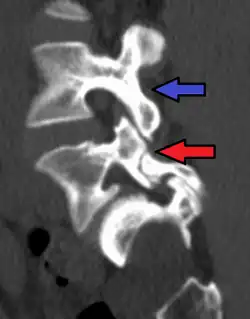

Spondylolysis is a bony defect or fracture within the pars interarticularis of the vertebral arch in the spinal column. The vast majority of spondylolysis occur in the lumbar vertebrae, however it can also be seen in cervical vertebrae.[3] The lumbar vertebra consist of a body, pedicle, lamina, pars interarticularis, transverse process, spinous process and superior and inferior articular facets, which form joints that link the vertebrae together. When examining the vertebra, the pars interarticularis is the bony segment between the superior and inferior articular facet joints located anterior to the lamina and posterior to the pedicle. Separation of the pars interarticularis occurs when spondylolysis is present in the spinal column.[14]

The scottie dog sign It was once used as a diagnostic sign in x-rays, for lumbar spondylolysis, but it is not commonly in use nowadays because of the advent of more sensitive diagnostic methods such as the CT scan and MRI scan. If spondylolysis is present, the pars interarticularis, or the neck of the dog, gives the appearance of a Scottish Terrier with a collar around its neck.[7]

X-Ray

X-rays (electromagnetic radiation) are projected through the body to produce an image of its internal structures. The radiation is more attenuated (absorbed) by the denser tissues of the body (i.e. bone) than the softer tissues (i.e. muscles, organs, etc.) creating a picture composed of shades of grey ranging from white to black. A vertebra with a fracture or defect of the pars interarticularis will have a dark mark through this region of bone. Since this is difficult to see on the AP (anterior posterior) x-ray view an oblique x-ray of the lumbar spine can usually identify the spondylolysis. If inconclusive a further CT scan can produce a 3-dimensional images to more clearly show the defect although the exam increases the patients radiation dose by at least an order of magnitude than plain x-rays.[16][17]

Commonly known as a CT Scan or CAT scan, this form of imaging uses x-rays to produce multiple cross-sectional images, or "slices", through a part of the body. This allows a physician to evaluate the body in greater detail than an x-ray allows. For this reason the CT scan is much more accurate in detecting spondylolysis than an x-ray. Bone scintigraphy combined with CT scan is considered the reference standard, which means that it is best at detecting spondylolysis.[16][18]